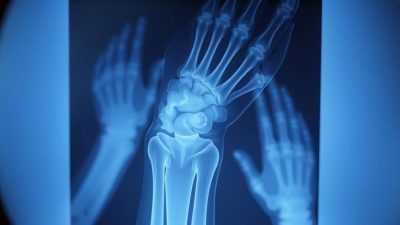

Pemeriksaan Radiologi dan Gambar Rontgen

Pemeriksaan radiologi, terutama gambar rontgen, memainkan peran kunci dalam memastikan diagnosa Fraktur Colles. Rontgen membantu dokter untuk memvisualisasikan kondisi tulang dan menentukan apakah ada fraktur atau tidak.

Dalam beberapa kasus, pemeriksaan lanjutan seperti CT scan atau MRI mungkin diperlukan untuk memperoleh gambaran yang lebih detail tentang kondisi tulang dan jaringan lunak sekitarnya.